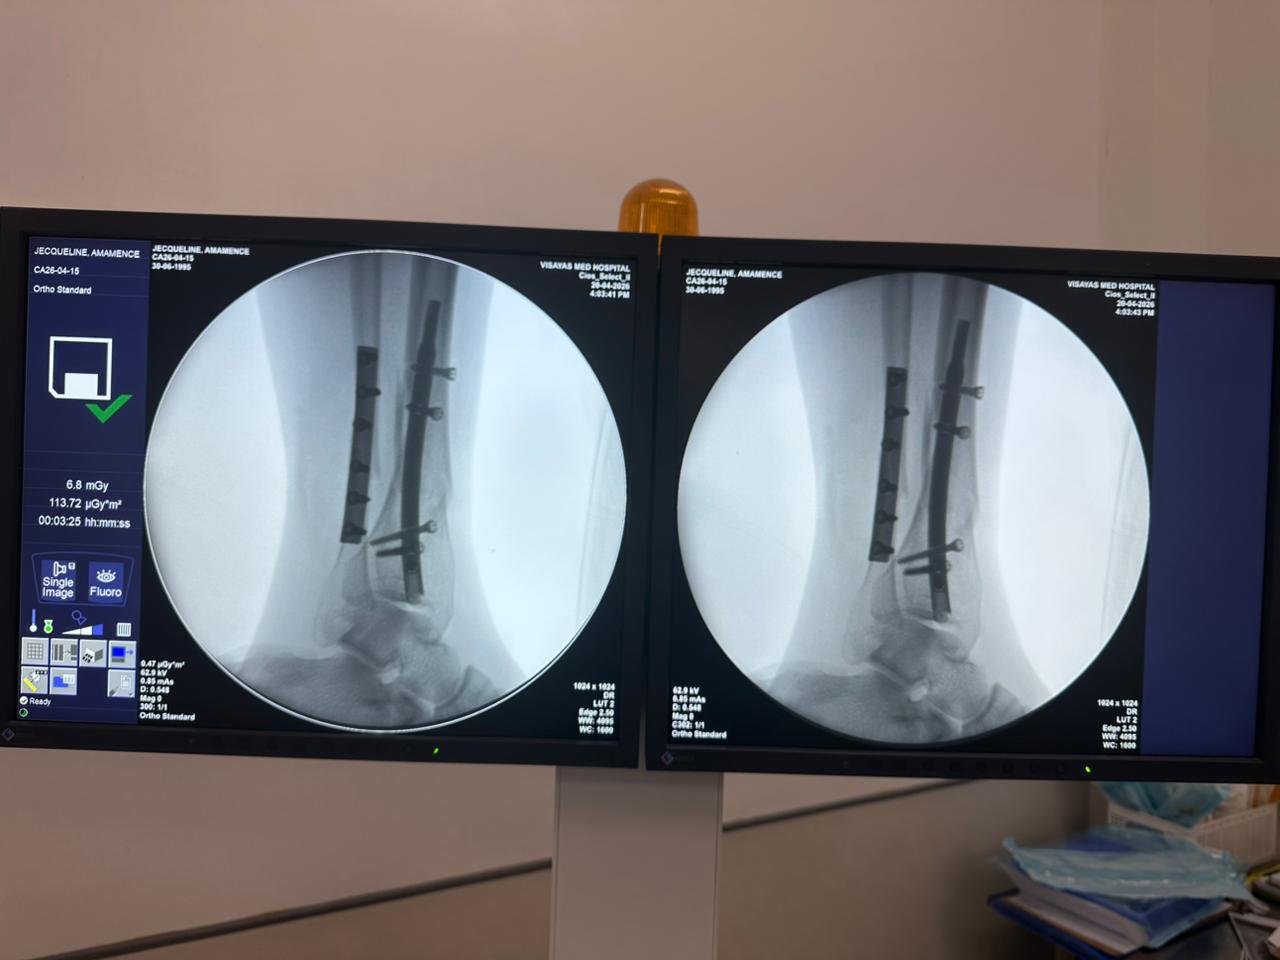

Radioscopie peropératoire de l'arceau, vues AP et latérales

Ce cas concernait une fixation tibiale distale à l’aide d’un clou tibial distal intramédullaire. La radioscopie peropératoire a confirmé la position du clou, des vis de verrouillage distales et de la fixation par plaque fibulaire.

cas-de-fixation-tibia-péroné-distal-CZMEDITECH

cas-d'ongle-tibial-distal-patient-de-31 ans-ap-view-czmeditech

cas-d'ongle-tibial-distal-patient-de-31 ans-vue-latérale-czmeditech